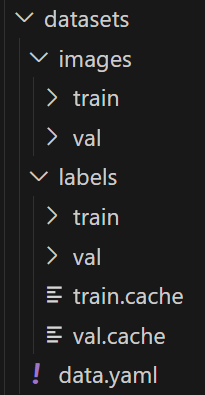

数据集配置文件data.yaml

train: .\datasets\images\train

val: .\datasets\images\val

test: .\datasets\images\test

nc: 1

names: ['Pneumonia']数据集制作流程